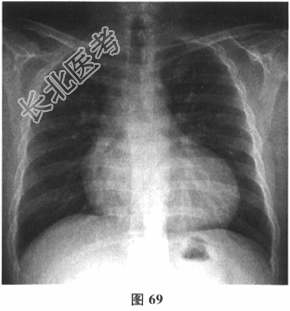

- 多项选择题2.[提示]血常规:白细胞12.4×109/L, 血红蛋白90g/L,血小板143×109/L。心电图示房扑2: 1下传(图68),心室率130次/分。胸片(图69): 心影增大。超声心动图(图70):心肌病变, 全心增大,左室心尖部存在较多肌小梁, 收缩末期非致密层与致密层之比为1:4, 左室舒张末内径70mm,左室收缩功能减低, LVEF32%,轻至中度二尖瓣关闭不全, 轻-中度三尖瓣关闭不全,下腔静脉增宽, 未见心包积液。